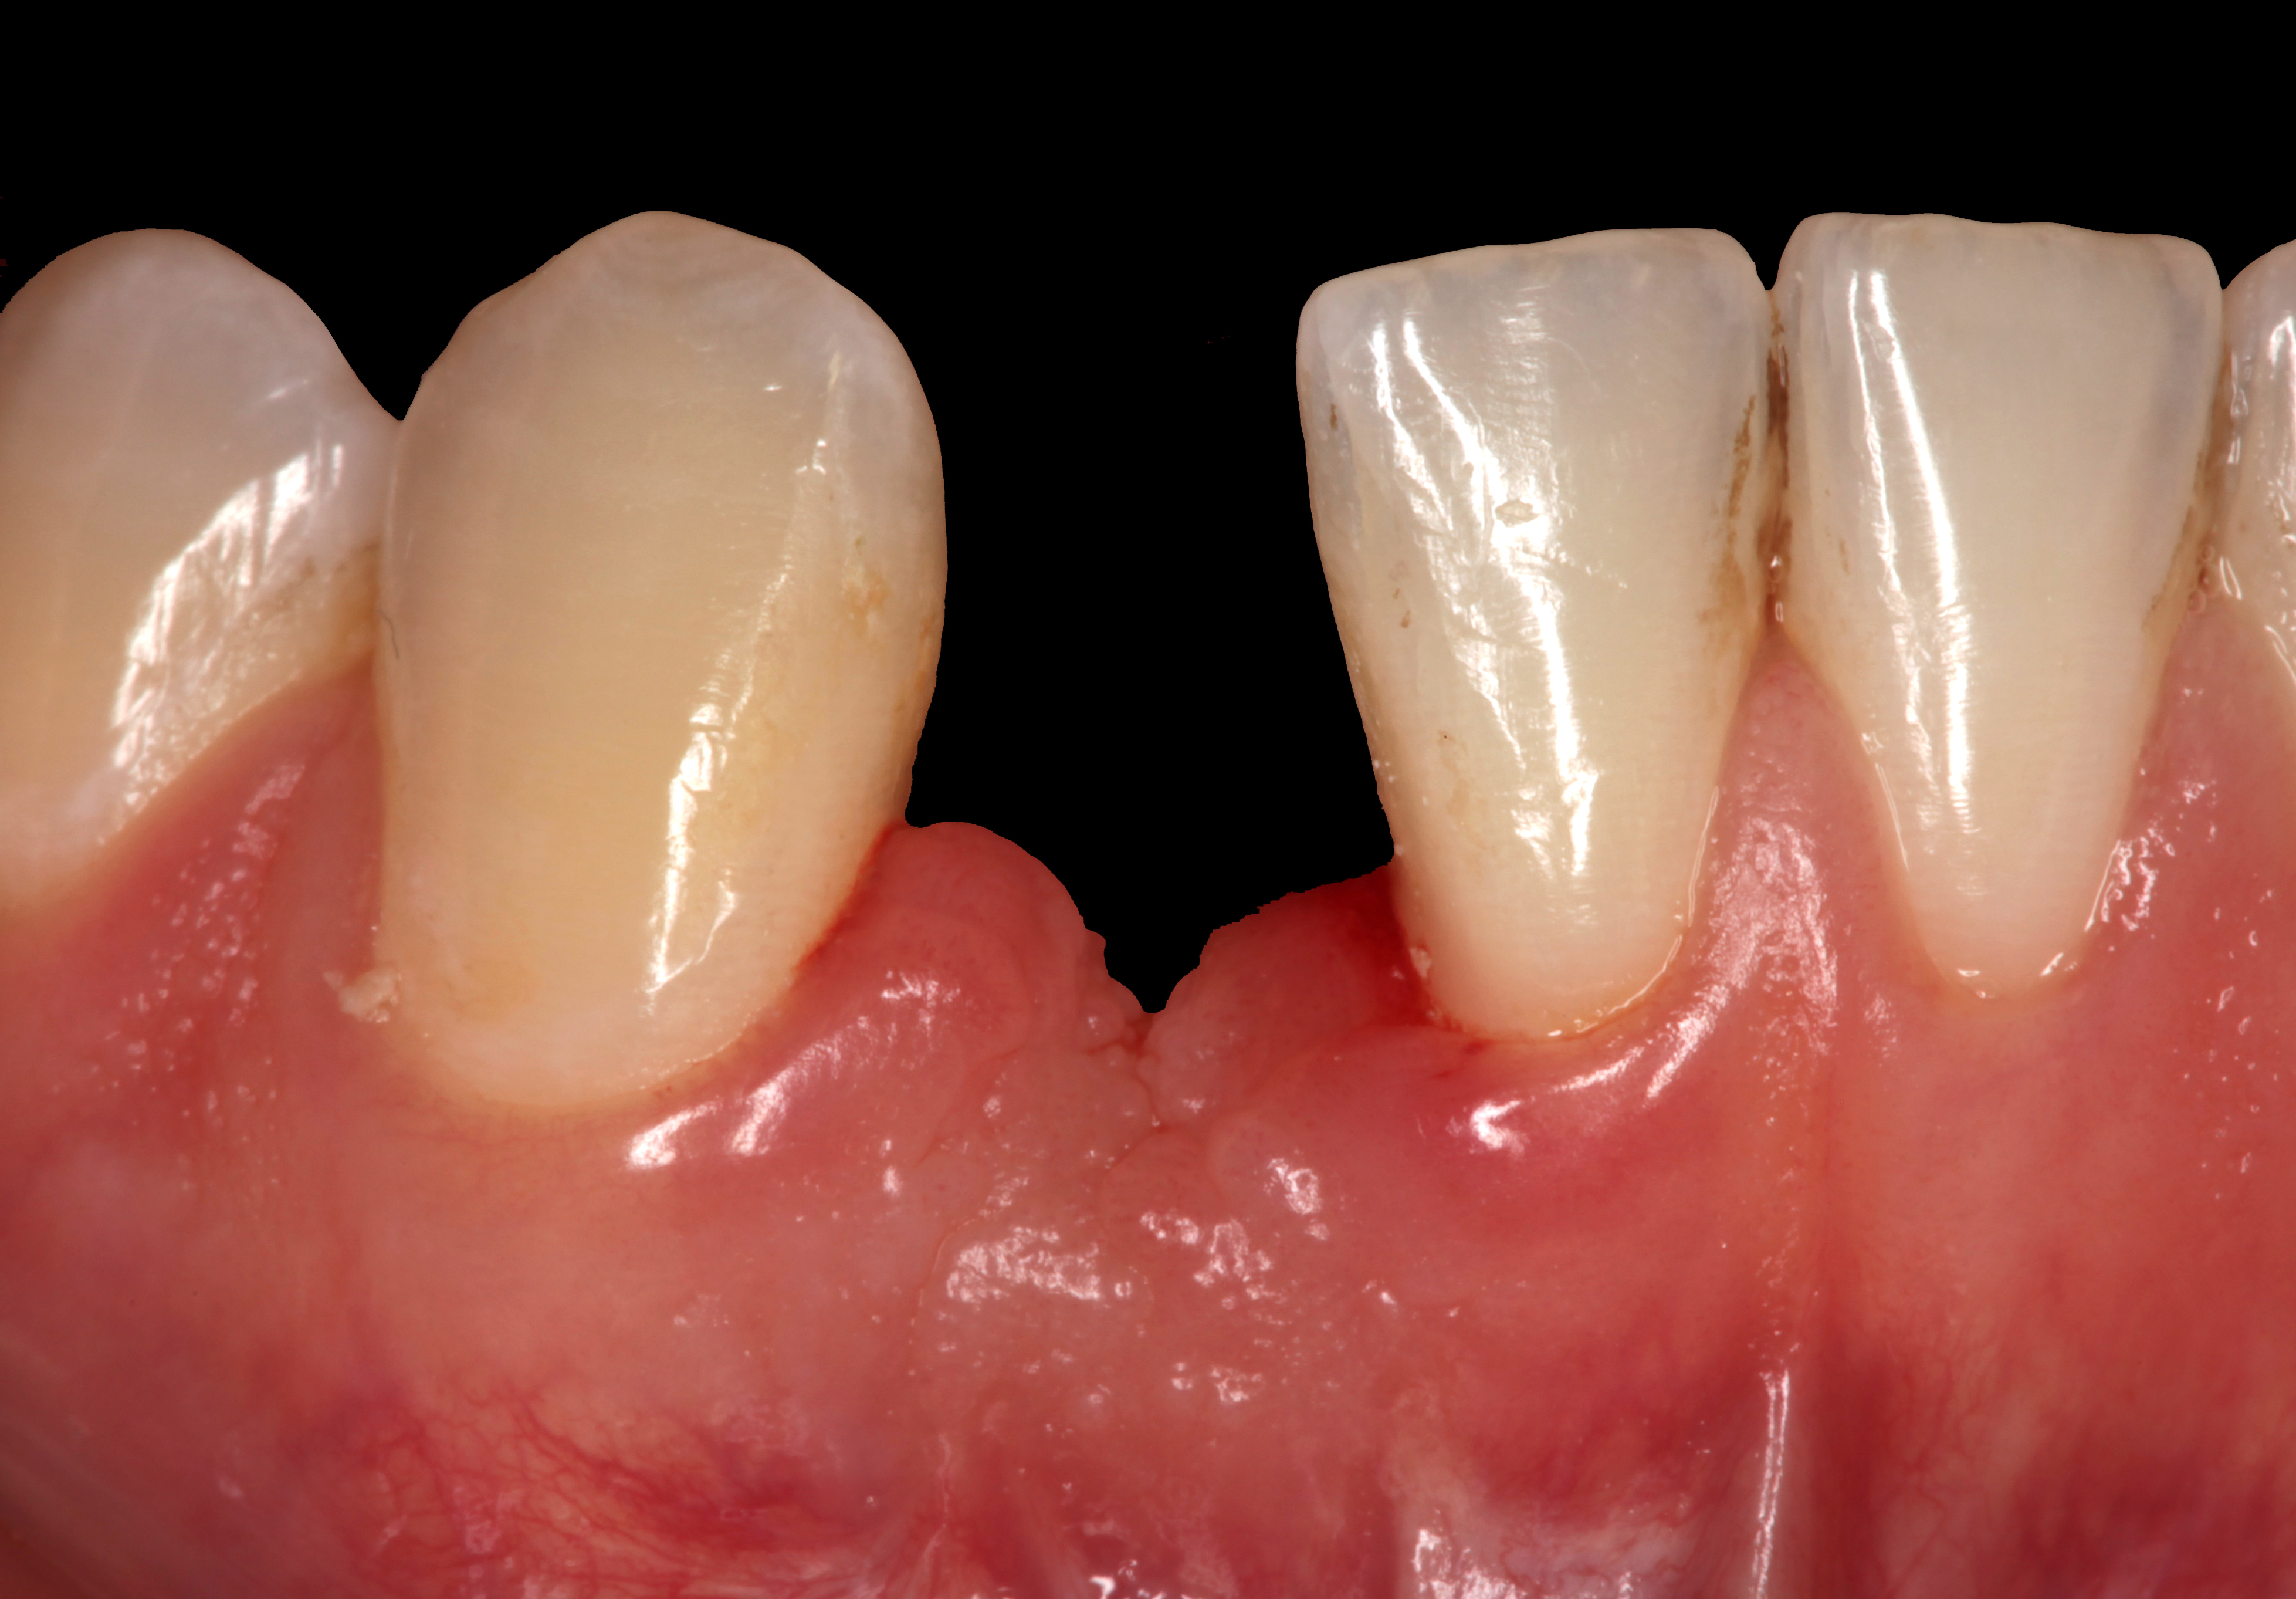

Problem: The implant is placed too facially, and there is significant labial gingival recession, contour change, and mucosal discoloration around the implant, abutment, and crown (Figure 3 and Figure 4). The implant attachment apparatus is intact and healthy, but the patient has a thin periodontal phenotype.

The following case report provides an example of this case scenario: A 28-year-old white female patient presented with her maxillary right lateral incisor significantly longer than the contralateral tooth following restoration of an existing crown that was 10 years old (Figure 3). The patient was dissatisfied with the esthetic appearance of the restoration due to the increased length, recession of the gingival tissues, and discoloration of the surrounding mucosa (Figure 4). Similar to case scenario No. 1, the first step in treatment was to decoronate the healthy implant by placing a flat surgical cover screw and employing a provisional resin-bonded-retained (RBR) prosthesis as a transitional fixed restoration (Figure 5 and Figure 6). The gingival augmentation in situ was allowed to take place for 2 to 3 weeks and was evaluated after that time (Figure 7).

Fig 3. A patient presented with a high smile line and midfacial recession of the maxillary right lateral incisor as evidenced by the increased tooth length compared with the contralateral lateral incisor.

Fig 4. Intraoral view of tooth No. 7 with the gingival zenith more apical than the adjacent central incisor and canine tooth.